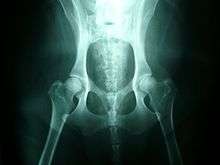

Dogs might exhibit signs of stiffness or soreness after rising from rest, reluctance to exercise, bunny-hopping or other abnormal gait (legs move more together when running rather than swinging alternately), lameness, pain, reluctance to stand on rear legs, jump up, or climb stairs, subluxation or dislocation of the hip joint, or wasting away of the muscle mass in the hip area. Radiographs (X-rays) often confirm the presence of hip dysplasia, but radiographic features may not be present until two years of age in some dogs. Moreover, many affected dogs do not show clinical signs, but some dogs manifest the problem before seven months of age, while others do not show it until well into adulthood.

The classic diagnostic technique is with appropriate X-rays and hip scoring tests. These should be done at an appropriate age, and perhaps repeated at adulthood - if done too young they will not show anything. Since the condition is to a large degree inherited, the hip scores of parents should be professionally checked before buying a pup, and the hip scores of dogs should be checked before relying upon them for breeding. Despite the fact that the condition is inherited, it can occasionally arise even to animals with impeccably hip scored parents.

In diagnosing suspected dysplasia, the x-ray to evaluate the internal state of the joints is usually combined with a study of the animal and how it moves, to confirm whether its quality of life is being affected. Evidence of lameness or abnormal hip or spine use, difficulty or reduced movement when running or navigating steps, are all evidence of a problem. Both aspects have to be taken into account since there can be serious pain with little X-ray evidence.